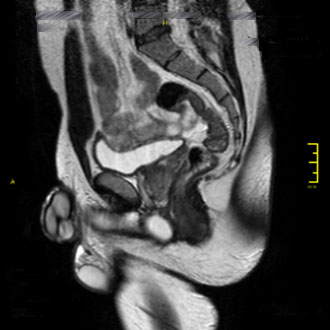

Die MRT des männlichen Beckens dient der Untersuchung von Harnblase, Prostata und den männlichen Geschlechtsorganen.

Die MRT liefert präzise Bilder der Weichteile und Gefäße und ermöglicht eine sichere Diagnostik – insbesondere bei unklaren oder chronischen Beschwerden.